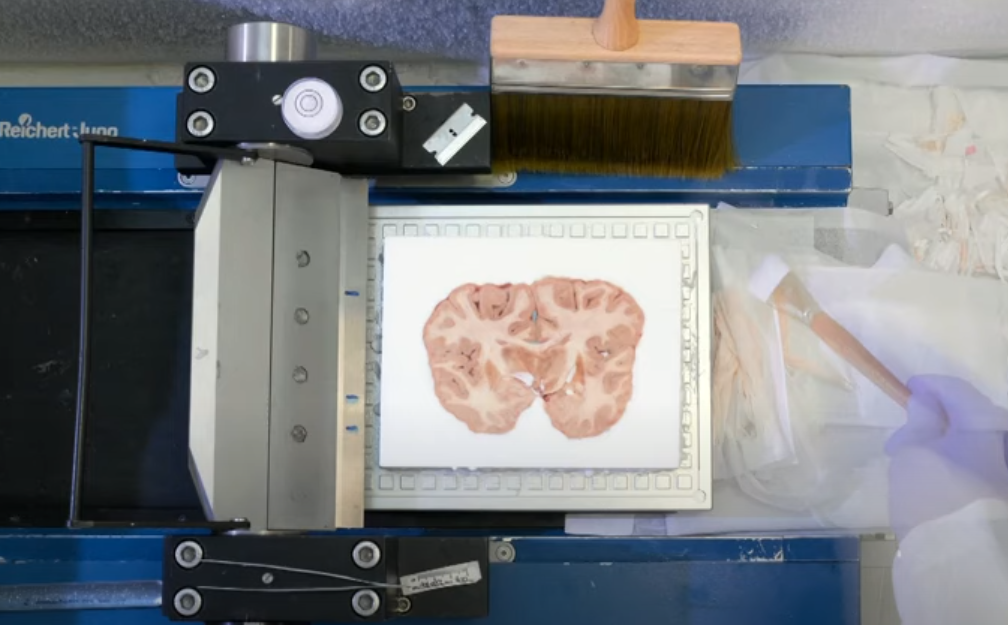

再将其切成薄片,制作成显微镜切片

随后进行染色和数字化,获取全脑的组织学信息

专家根据被染色的细胞聚集的情况找到组织的边界,作为随后定位和分割的解剖参考